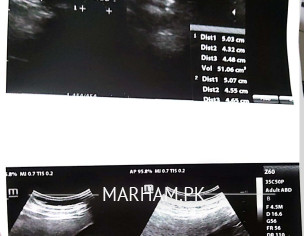

scan report is attached